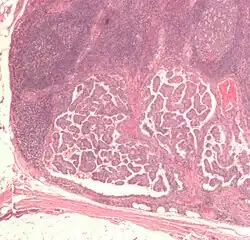

| Micrograph of a papillary thyroid carcinoma demonstrating diagnostic features (nuclear clearing and overlapping nuclei). | |